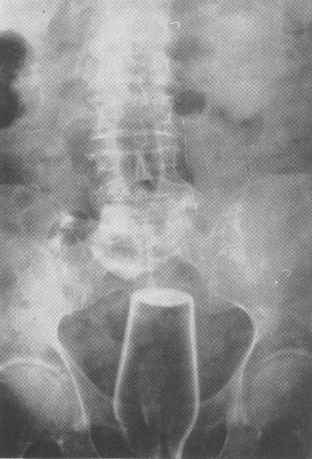

Odd Ass Objects Tribute to SOFREP reader Mr. Mason F.

It’s astonishing how many people are slipping whilst naked these days and falling on a stunning array of disparate objects and having them end up in their rectums. I’m baffled. Doctors will tell you that slipping and falling while naked is the primary explanation offered by patients in emergency rooms for how that box of Tide — for instance — ended up in their ass. Why do Docs even ask how it happened? Does the answer have a bearing on how the object will be removed — no.